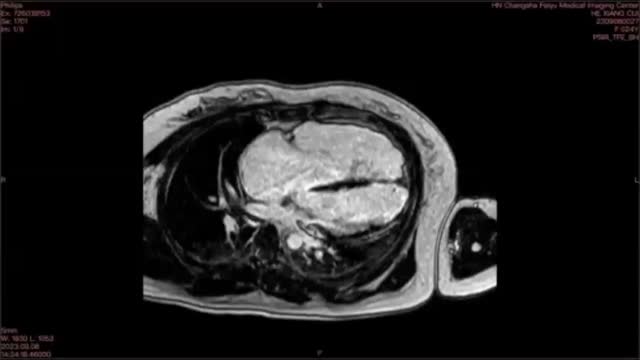

A previously healthy 25-year-old female presented to the emergency department with 5 h of palpitations and lightheadedness. Upon admission, the electrocardiogram (ECG) showed sustained ventricular tachycardia (VT) of left bundle branch block (LBBB) morphology with superior axis (Fig. 1A). The VT episode was terminated by intravenous amiodarone. Subsequent ECG after cardioversion revealed T wave inversion in all precordial leads and epsilon wave in leads V2 and V3 (Fig. 1B). Of note, her father died suddenly at the age of 38. Further cardiac magnetic resonance (CMR) revealed global hypokinesia in the free wall of the right ventricle (RV), as well as regional hypokinesia in the left ventricular apical wall (Fig. 1C, D, Supplement data Video 1). Notably, right ventricular ejection fraction was only 3%. Moreover, evidence of myocardial fibrosis was observed at the apex of the left ventricle (LV), with no such findings noted in the RV (Fig. 1E, Supplement data Video 2). Genetic testing revealed a mutation in the PKP2 gene. Based on the findings mentioned above, the diagnosis of arrhythmogenic right ventricular cardiomyopathy (ARVC) with LV involvement was established. The patient was started on metoprolol and was advised to undergo implantable cardioverter defibrillator (ICD) implantation.